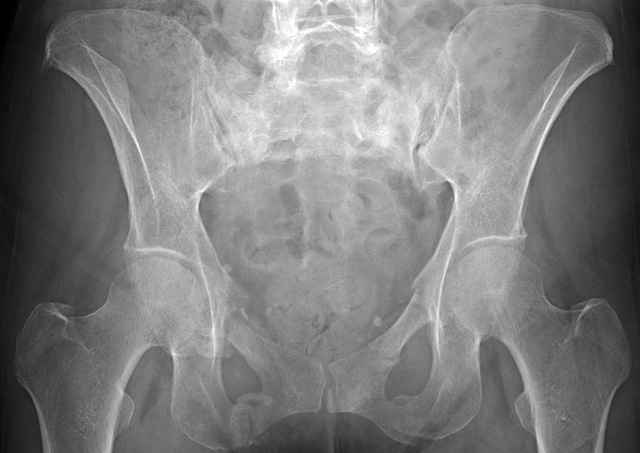

hello everyone, attached are images of a 59 yo female, admitted today after motor vehicle collision. Pt states her pelvis has been very painful ever since she fell on her buttocks from ground level a little over a year ago. medical history significant for scleroderma, raynauds syndrome, and COPD. no past surgeries.

pt states she is very limited in walking ability secondary to pain. she requires a cane or a walker. friends and family do her shopping. the pain is localized primarily around left upper groin. she points to the rami region.

the question is if her medical history is contributing to the nonunions, and if anyone would consider surgical intervention, or is there some other successful intervention?

Here are a recent patient’s example slides...

54 yo Female Fell c/o Pain

Initial Films

?Instability on Exam - Limited by Pain

NonOp Initial Mgmt